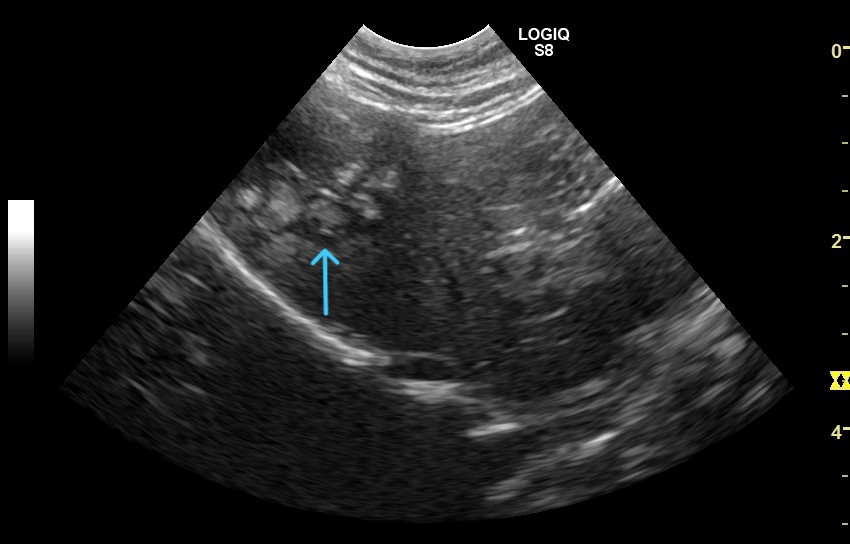

写真中矢印 胆管に詰まった胆石

写真中矢印 手術所見 拡張した総胆管